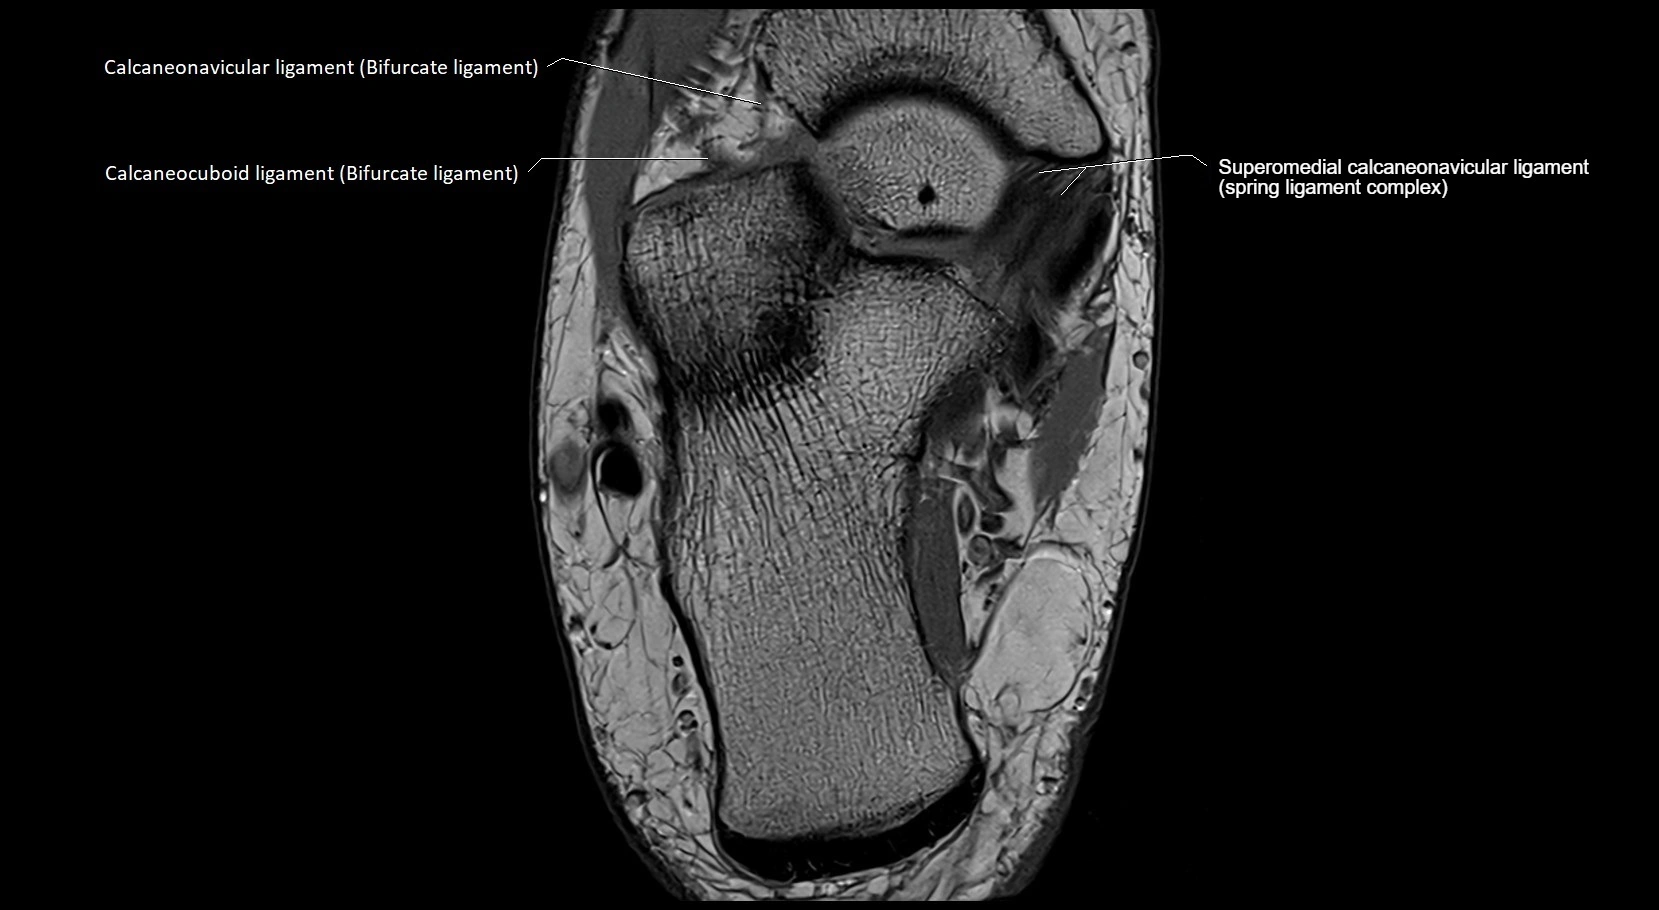

MRI image

image